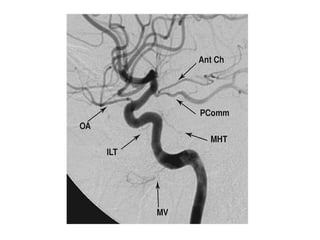

Ophthalmic artery

Lateral projection of a left common carotid artery injection that displays the

order of branching in the intracranial carotid including 1: ophthalmic , 2:

posterior communicating , 3: anterior choroidal and 4: anterior cerebral

arteries